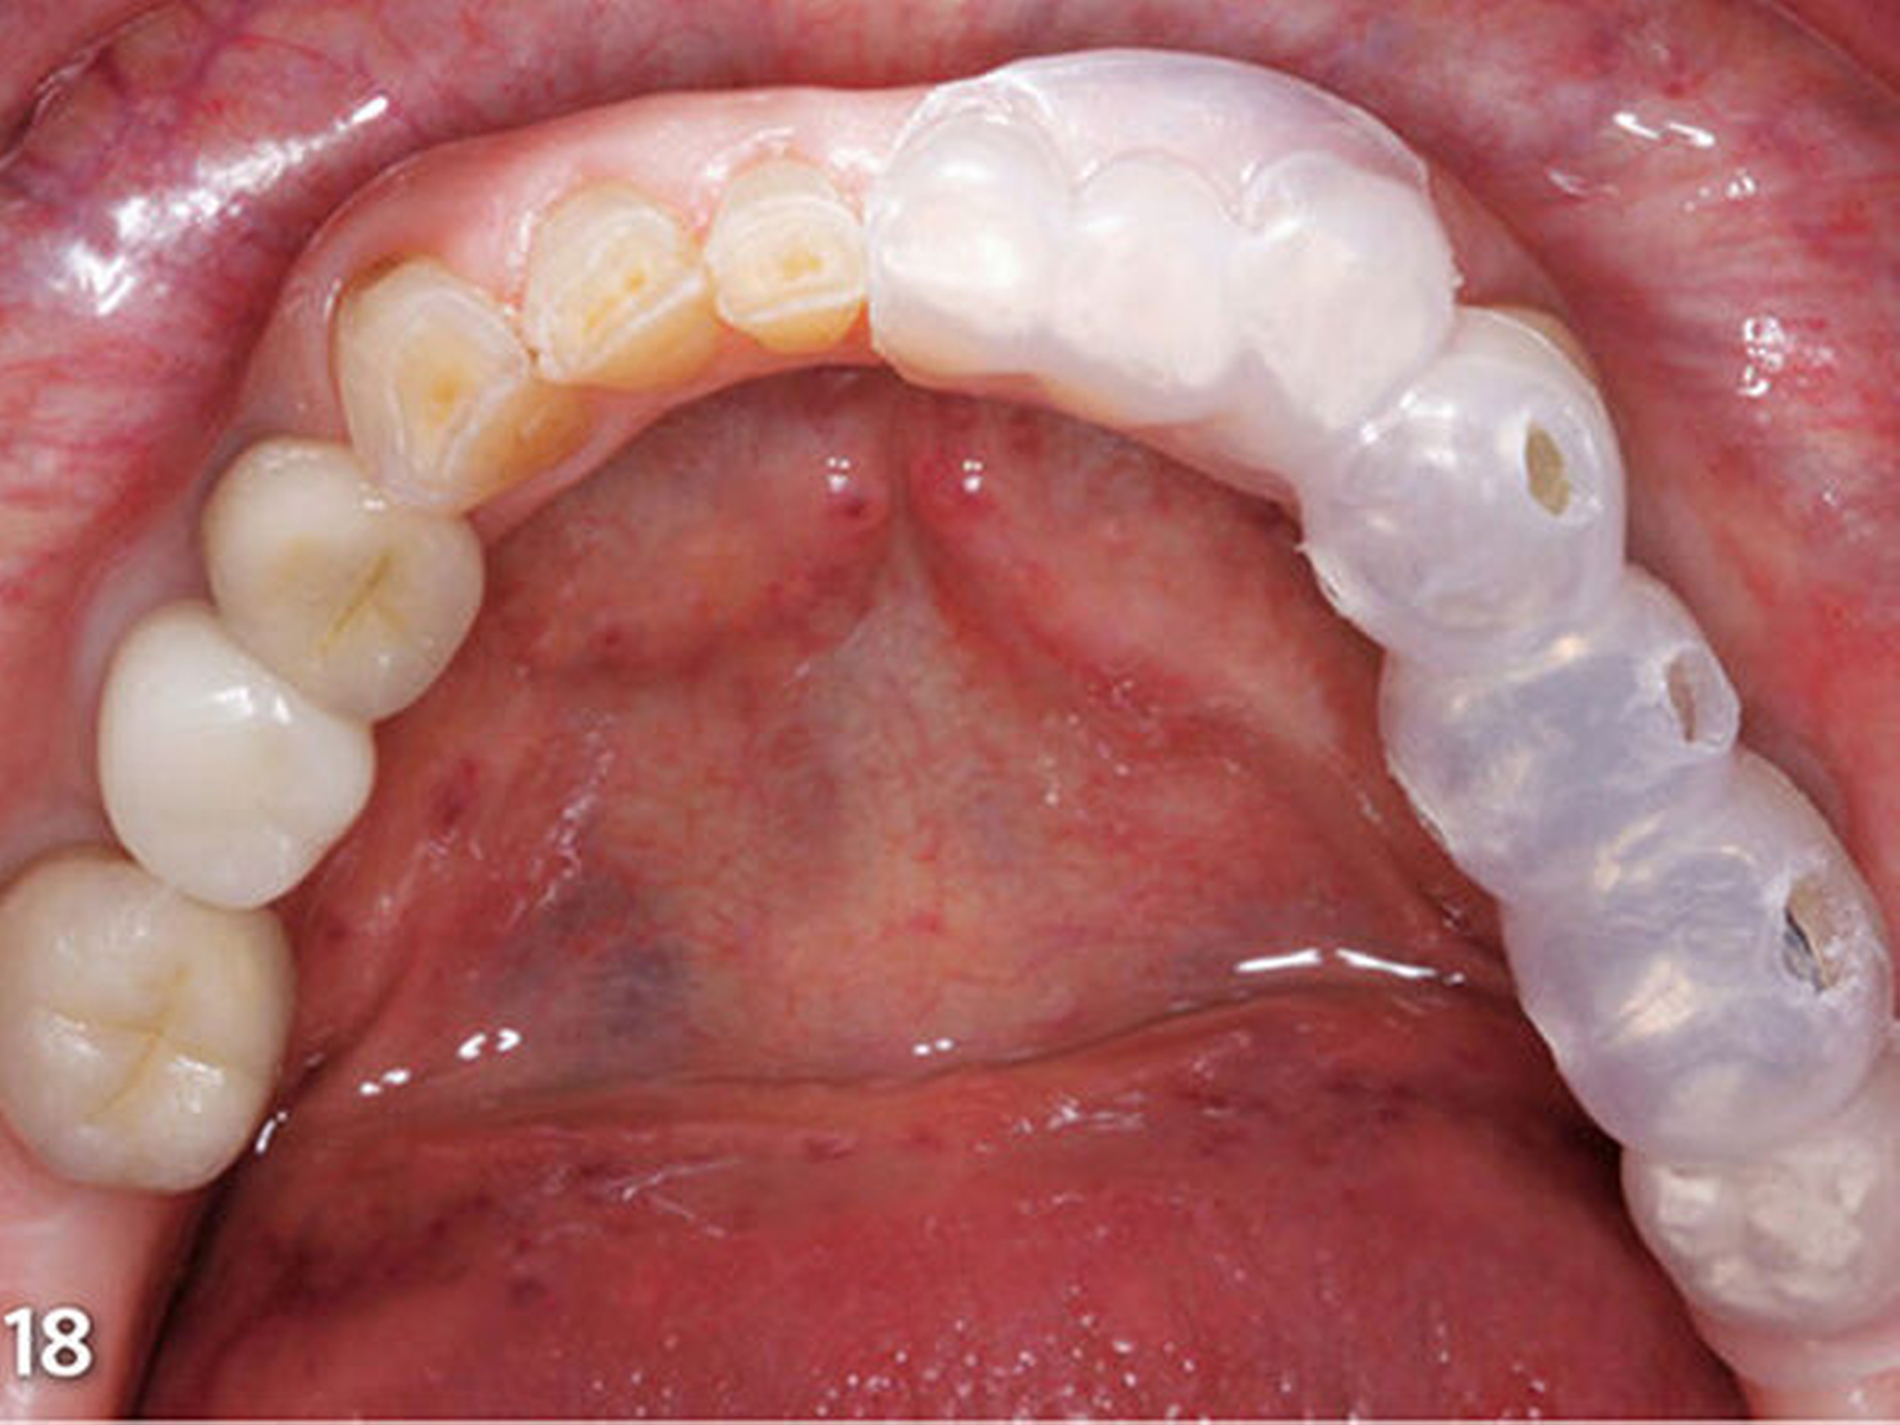

Vierte zahnärztliche Sitzung: Für die bessere Handhabbarkeit wurden die beiden ersten Schienen (Schiene1 und2) zum Aufbau der Seitenzähne im Bereich der Front jeweils in eine linke und eine rechte Hälfte getrennt. Das erste Schienensegment (Schiene1) wurde intraoral auf seinen perfekten spannungsfreien Sitz und die eindeutige Abstützung am letzten Molaren und im Frontzahnsegment hin kontrolliert (Abb.18). Ebenso wurde die korrekte Lage der bukkalen Einspritzöffnungen verifiziert (Abb.19).

In korrekter Endposition stellt die Schiene die verloren gegangene Zahnhartsubstanz als Hohlraum zwischen Schienenkunststoff und okklusalen Restzahnanteilen dar (Schmidlin et al. 2009c). Nachdem die Schiene zum Schutz der Weichgewebe, an der selektiv die vorzubehandelnden Bereiche freigeschnitten wurden, intraoral positioniert wurde (Abb.20), erfolgte mit einem intraoralen Sandstrahlgerät die tribochemische Silikatisierung (CoJet, 3M Espe) im Bereich der okklusalen Oberflächen der vorhandenen Restaurationen (Abb.21) (Frankenberger et al. 2000, 2014; Matinlinna 2013; Ozcan 2003). Nach Entnahme der Schutzschiene wurde auf die derart silikatisierten Oberflächen sorgfältig ein Silan aufgetragen (Abb.22) (Blatz et al. 2003; Kupiec et al. 1996).